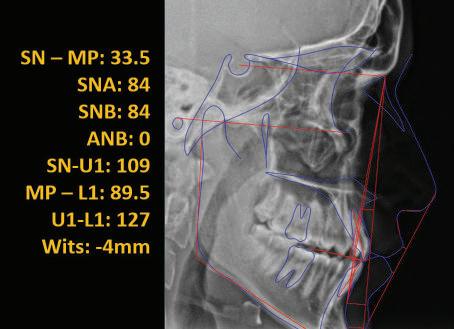

20 Dental Tribune Bulgarian Edition / октомври 2022 г. П ациентите със завършен растеж и скелетни проблеми обикновено представляват предизвикателство за ортодонт ската практика. Необходимостта от изваждане на зъби в комбинация с особеностите на възрастовата ортодонтия изисква особено внима ние. Фокусът върху критично важното значение на позицията на долните резци във връзка с дългосроч ната стабилност и постигането на оптимални оклузални взаимоотношения при затварянето на екстракционните пространства лесно може да излезе извън контрол. Когато към тези чисто кли нични проблеми се добави и стресът от натоваре ната практика, предизвикателството става още по-голямо. Всички тези фактори налагат използ ването на доказан подход с ясни и последовател ни стъпки, в което се разкрива силата на дисциплината „Алекзандър“ – предвидим протокол през целия процес на елиминиране на ротациите, ниве лиране на дъгите, затваряне на екстракционните пространства и финализиране на случая. Именно такъв е и случаят, който презентираме –екстракционен, скелетен клас 3 при възрастен па циент, лекуван по системата „Алекзандър“. ПРЕДВИДИМИ РЕЗУЛТАТИ ПРИ ПАЦИЕНТИ СЪС ЗАВЪРШЕН РАСТЕЖ И СКЕЛЕТЕН КЛАС 3, ИЗПОЛЗВАЙКИ ЕКСТРАКЦИОННО ЛЕЧЕНИЕ ПО ДИСЦИПЛИНАТА „АЛЕКЗАНДЪР“ Д-р Радой Димитров, България Преди започване на лечение клиничен случай | ортодонтия Фиг. 1а–1e Преди започване на лечение. Пациентът пристига в практиката с основното оплакване от невъзмож ност за нормално дъвчене. Снета е цялата необходима диагностична ин формация. Фиг. 1f–1h Снимки в профил и анфас. Фиг. 1i–1k Панорамна снимка, телерентгенография и анализ на телерент генография. Фиг. 1а Фиг. 1d Фиг. 1f Фиг. 1g Фиг. 1h Фиг. 1e Фиг. 1b Фиг. 1c Фиг. 1i Фиг. 1j Фиг. 1k

closed.

21Dental Tribune Bulgarian Edition / октомври 2022 г. ДИАГНОСТИЧНИ РЕЗУЛТАТИ: 1. Възраст на пациента: 21 години 2. Скелетен клас III (ANB 0) 3. Зъбен клас 3 4. Ръбцова захапка във фронта, кръстосана в дисталните участъци 5. Тясна горна челюст 6. Overjet – 0 мм, Overbite – 0 мм 7. Несъответствие на горната с долната средна линия 8. Единични контакти в ЦО 9. Хиподивергентен тип на растеж SN/MP – 33.5 10. Неравен гингивален контур 11. Неравна линия на усмивката 12. Тенденция за рецесии в долен фронт ПРЕПОРЪЧИТЕЛНО ЛЕЧЕНИЕ: Пълно ортодонтско лечение с метални брекети „Алекзандър“ Корекция на клас 3 захапката в областта на кучешките зъби с екстракция на първите пре молари в долна челюст Корекция на кръстосаната захапка в дистални участъци Коригиране на ръбцовата захапка във фронта Подобряване на ОJ и OB на пациента Стрипинг в долен фронт Подреждане на зъбите в горната и долната челюст Професионално хигиенизиране и профилактични дентални прегледи са препоръчителни на всеки 6 месеца. 1-ви месец След 1 месец са залепени брекети в горната челюст – поставена е еластична дъга. 016 NiTi. В долната челюст са елиминирани ротациите, поставена е стоманена дъга. 016SS, закалена с ток, и еластична верижка за затваряне на пространствата. 3-ти месец В долната челюст е поставена трета дъга – 17 x 25 NiTi с къси лигатури и верижка

Dental Tribune Bulgarian Edition / октомври 2022 г.22 клиничен случай | ортодонтия 14-и месец В горната и долната челюст са поставени последни стоманени дъга с омега луп и тай бек – 17 x 25 SS с четвъртито сечение. Назначени е ластик за средната линия в комбинация с клас 3 ластик (1/4”, 6 1/2 oz). Контролни рентгенографии 13-и месец Екстракционните пространства са затворени. Направена е контролна панорамна снимка за оценка позицията на корените. Взето е решение за презалепване на брекетите на 12, 22 и пръстените на 36 и 46. 21-ви месец Средната линия в горната и долната челюст съвпадат. Ластиците са спрени. Свалени са пръстените и брекетите в горната и долната челюст, зигзаг ластици не са използвани поради благоприятните оклузални взаимоотношения. Фиг. 11j Ортопантомография в края на лечението. Фиг. 11k Телерентгенография след края на лечението. Фиг. 11l Анализ на телерентгенографията след лечението. Фиг. 11m Последователност на дъгите в горната и долната челюст Фиг. 11n Суперимпозиция на PreOp и PostOp ортопантомографии. 10-и месец Затварянето на пространствата е предвидимо и контролирано, без да се отварят пространства в зъбната дъга. Фиг. 8a Фиг. 8b Фиг. 8c Фиг. 8d Фиг. 8e Фиг. 10a Фиг. 10b Фиг. 10c Фиг. 10d Фиг. 10e Фиг. 9a Фиг. 9b Фиг. 9c Фиг. 9d Фиг. 9e Фиг. 9f Фиг. 11a Фиг. 11f Фиг. 11j Фиг. 11l Фиг. 11m Фиг. 11n Фиг. 11k Фиг. 11g Фиг. 11h Фиг. 11i Фиг. 11b Фиг. 11c Фиг. 11d Фиг. 11e

Dental Tribune Bulgarian Edition / октомври 2022 г. 23клиничен случай | ортодонтия реклама Лечението е продължило 21 месеца. Проведено е домашно избелване с индивидуални шини. За автора: Д-р Радой Димитров завършва с отличие Факултета по дентална медицина към МУ–София през 2015 г. В продължение на 5 години работи в няколко водещи практики в София, като през 2019 г. заедно със своята съпру га д-р Траяна Димитрова основават собствена практика в гр. Гоце Делчев –Dimitrovi Dental Care. Посещава редица курсове за повишаване на квалификаци ята, но най-сериозен тласък в развитието на ортодонтската си практика получава след завършването на комплексната ортодонтска програма, воде на от д-р Иван Горялов, базирана на дисциплината „Алекзандър“ – система с повече от 50 години опит в целия свят. Д-р Димитров е член на Българския изследователски клуб „Алекзандър“. Взе ма участие като гост-лектор в симпозиума с международно участие The Power of the Alexander Discipline, който се проведе на 14–15.05.2022 г. С д-р Ди митров можете да свържете на тел. +359885 252 025. Заключение Представеният случай е ярък пример за възможностите и красо тата на дисциплината „Алекзандър“ – приложен е утвърден под ход с ясни правила и са постигнати очакваните цели. Резулта тът ще бъде дългосрочно стабилен, тъй като са спазени всички правила, които се отнасят към максимално комфортната пози ция на зъбите в края на лечението. Постигнати са красива усмив ка и стабилна оклузия. ПОСТИГНАТИ РЕЗУЛТАТИ ОТ ЛЕЧЕНИЕТО 1. Коригирана ръбцова захапка 2. Коригирана клас 3 захапка в областта на ку чешките зъби 3. Коригирана кръстосана захапка в дисталните участъци 4. Коригиран овърджет и овърбайт 5. Разширена е горната зъбна дъга 6. Подредени зъби в горната и долната челюст 7. Постигната е стабилна захапка с множество контакти в ЦО 8. Драматично е подобрена дъвкателната функ ция 9. Подобрена е линията на усмивката ДРУГИ ПРОВЕДЕНИ ДЕНТАЛНИ ПРОЦЕДУРИ 1. Домашно избелване на зъбите 2. Екстракция на мъдреците Фиг. 12a Фиг. 12b Фиг. 12c Фиг. 12eФиг. 12d Фиг. 12f Фиг. 12g Информация за дати, цени и отстъпки www.bracescourses.com 0889 22 55 01 Практически курсове лектор д-р Иван Горялов Дисциплината „Алекзандър“ ПЪТЯТ КЪМ СУПЕРУСМИВКИТЕ 100% връщане на цялата сума, ако не сте удовлетворени след преминаване на Ниво 1 Директно и индиректно залепяне на брекети Анализ, диагноза и план на лечение Лечение на клас 2 дълбока захапка Екстракционно лечение Лечение на клас 3 отворена захапка НИВО 5НИВО 1 НИВО 2 НИВО 3 НИВО 4